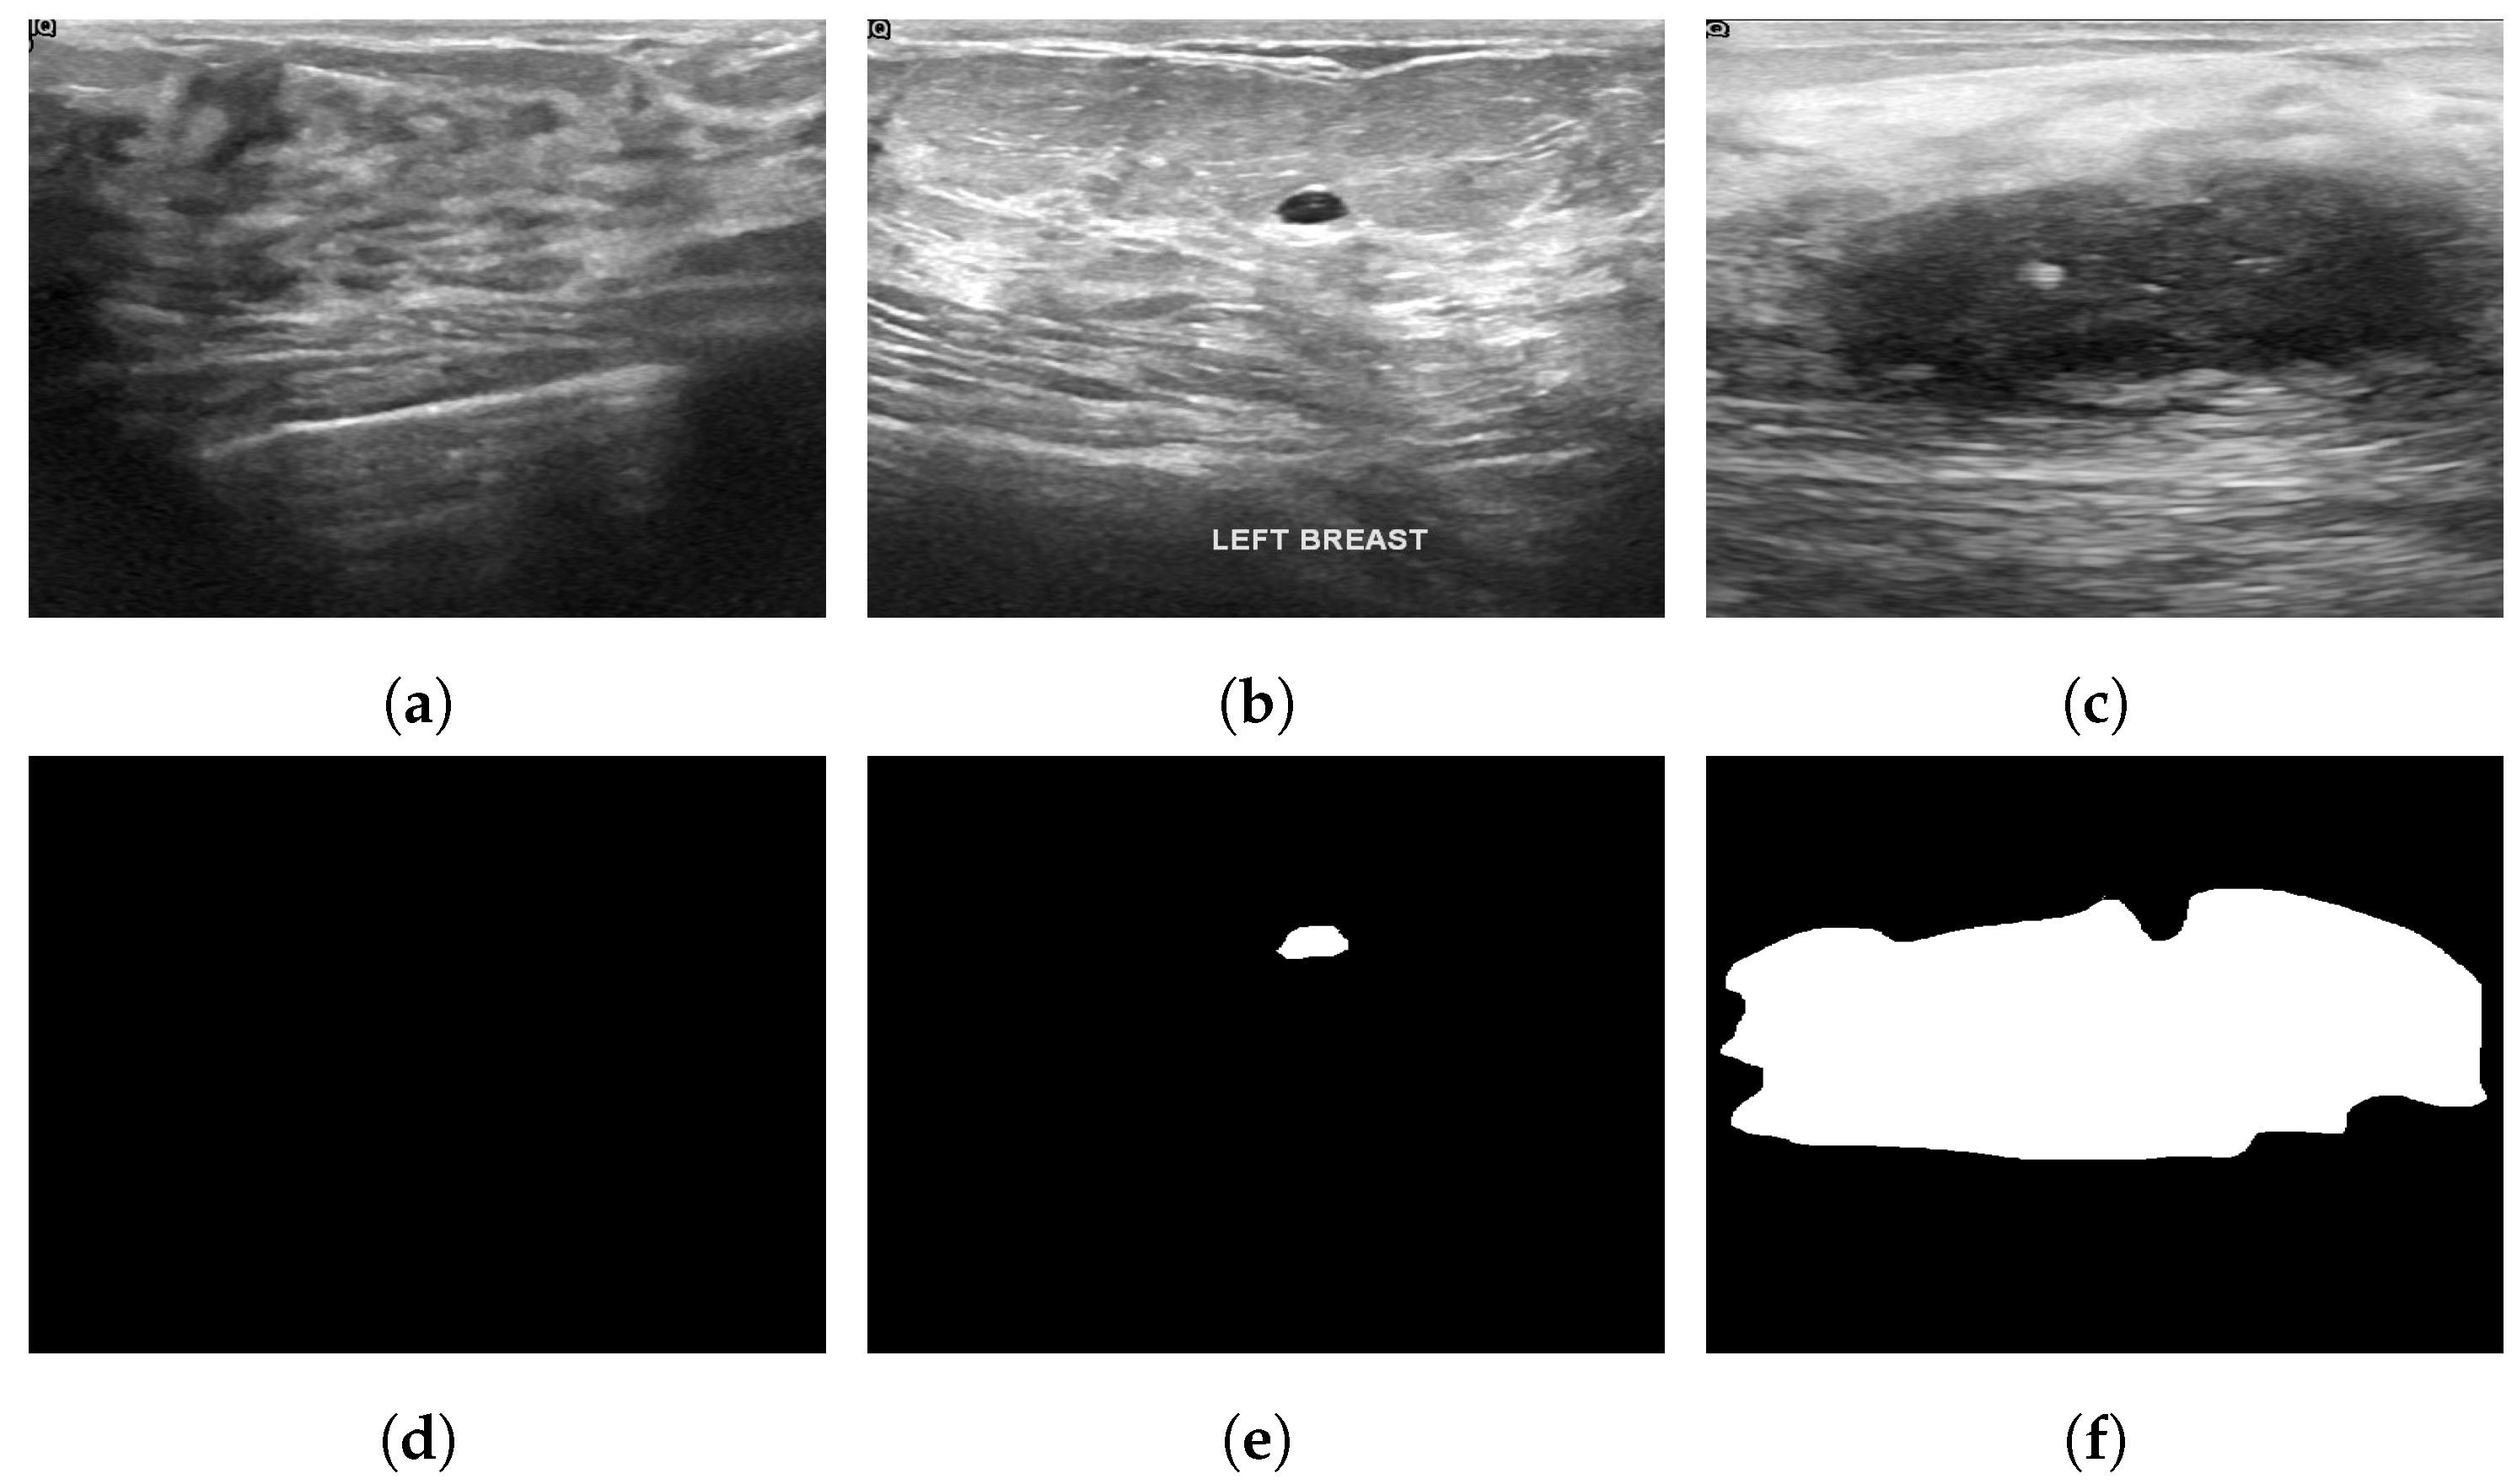

3.11. Breast Ultrasound Dataset

The Breast Ultrasound Dataset [25] was collected in 2018 and stored in DICOM format at Baheya Hospital, Cairo, Egypt. A LOGIQ E9 ultrasound system and a LOGIQ E9 Agile ultrasound system were used in the scanning process. Using a DICOM converter application, the images were converted into PNG format. All images were preprocessed by removing duplicate images and unused boundaries from the images. A total of 600 female patients between the ages of 25 and 75 were included in this dataset. The dataset was divided into three classes: normal, benign and malignant, with 133, 487 and 210 images, respectively. Each image is in PNG format and is 500 pixels by 500 pixels. There is also a ground truth available for each image. Figure 6 illustrates some sample images from the Breast Ultrasound dataset.